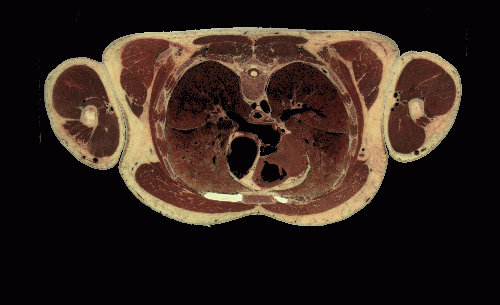

brain, the area of the nose was outside the scanner's field of view. As you can see in the second image,

the nose remains perfectly intact in the cryosection data.

Slice from Head Region